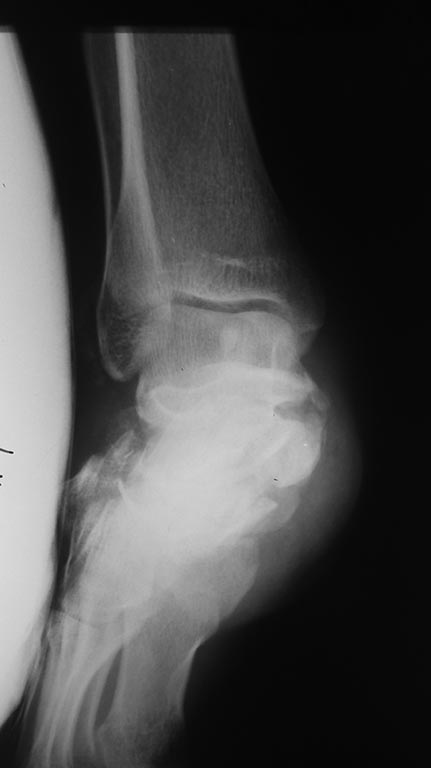

Имя     : 20170317_184718.jpg

Тип     : image/jpeg

Url     : http://weborto.net:8080/pipermail/ortho/attachments/20170320/7e16afb9/attachment-0005.jpg